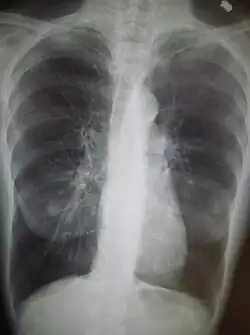

Una radiografia del torace e un esame emocromocitometrico completo possono essere utili per escludere altre condizioni patologiche presenti al momento della diagnosi.[51]

I segni caratteristici alla radiografia sono polmoni iper-espansi, diaframma appiattito, aumento dello spazio aereo retrosternale e la presenza di bolle. La presenza di tali segni può aiutare a escludere altre malattie polmonari, come la polmonite, l'edema polmonare o uno pneumotorace.[23]

Radiografia del torace che mostra una severa BPCO. Si notino le ridotte dimensioni del cuore in confronto a quelle dei polmoni.